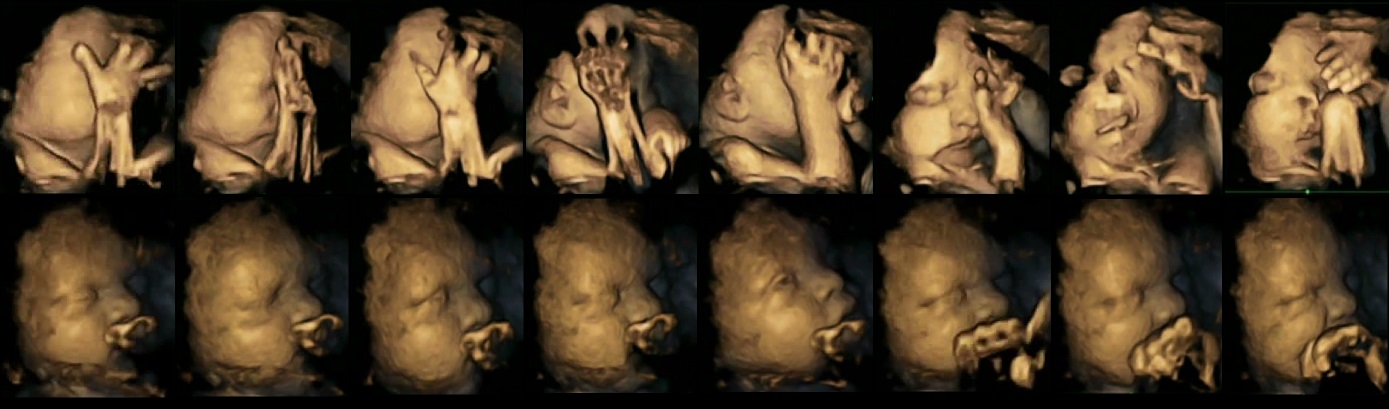

《小兒科醫學會雜誌》〈Acta Paediatrica〉刊載這份英國杜倫大學(Durham University)與蘭開斯特大學(Lancaster University)共同合作的最新研究,這個為期12周的研究共分成四個階段,觀察20位寶寶的立體超音波,其中四位母親每天抽超過14根菸,其餘的母親則沒有抽菸的習慣。研究發現,所有寶寶剛出生時健康狀況都良好,不過,懷孕期間在母親肚子裡間接吸菸的胎兒,碰觸臉部的動作比較多,嘴部動作更是明顯多出很多。

研究團隊認為,這是因為經由母親吸菸的胎兒,中樞神經發展速度和沒有吸到菸的胎兒速度不一樣,中樞神經控制著大部分的肢體動作以及細微的臉部動作。過去也有研究指出,經由母體吸菸的寶寶,開始說話的時間明顯較晚。